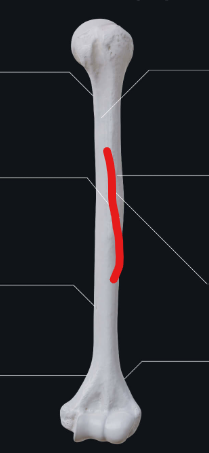

deltod tuberosity